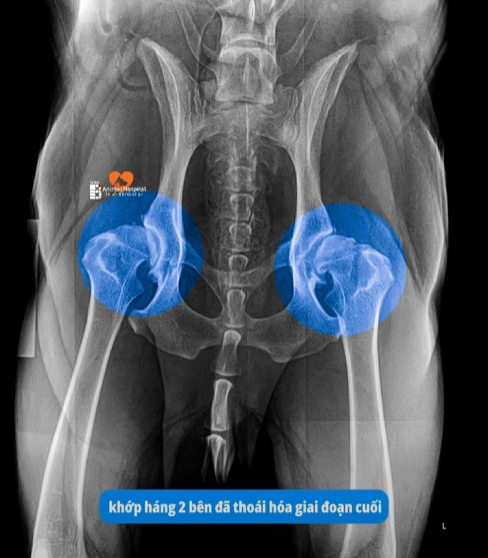

Thoái hóa xương khớp (ở chó lớn tuổi): Khi chó già đi, lớp sụn ở khớp háng bị bào mòn. Mỗi bước đi khiến hai đầu xương cọ xát vào nhau gây đau đớn tận cùng.

Nếu kết quả chụp phim cho thấy bé bị gãy xương, đứt dây chằng hay thoái hóa khớp háng nặng, các phương pháp nắn bóp thông thường sẽ không có tác dụng. Lúc này, DỊCH VỤ THAY KHỚP HÁNG THR chính là giải pháp dứt điểm, giúp bé lấy lại những bước chạy nhảy vui vẻ như ngày đầu.